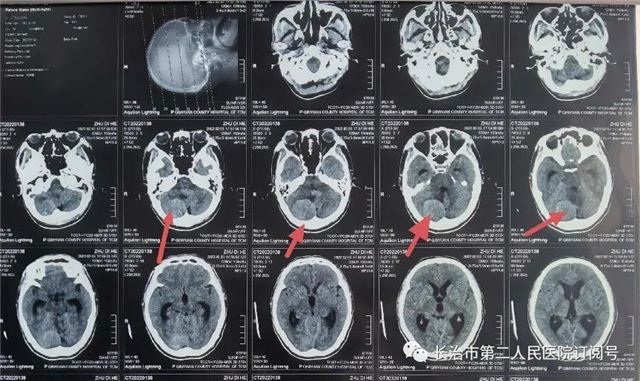

▲CT发现左额叶占位,局部脑组织水肿

术前检查见右额占位,强化明显,患者血糖27mmol/L,老慢支、肺气肿四十余年,血气分析:氧分压55.7%(参考值83-108%),氧合指数169mmHg(参考值400-500mmHg),经科室讨论,内分泌科、呼吸内科、心内科、麻醉科评估手术风险后在全麻下行开颅颅内肿瘤切除术。

▲术后复查肿瘤全切,术野干净